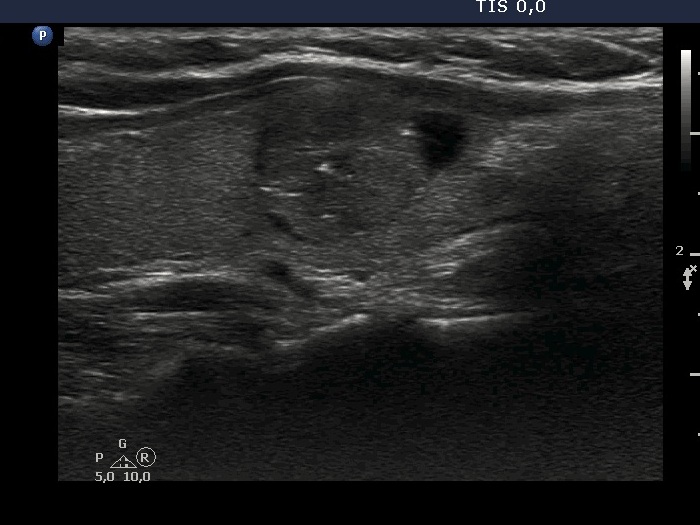

Ultrasonography. The thyroid was echonormal or minimally hypoechoic. There was a moderately hypoechoic nodule which had a cystic portion in the lower part. The nodule had lobulated margins and contained different hyperechoic figures. Beside figures caused either by posterior enhancement of proliferation of connective tissue, several ambiguous. bright granules were also found. Compared with the first measurement, the nodule is increased by more than 75% in volume.

Comment. It is worth looking at the video several times and analyzing the various echogenic foci.